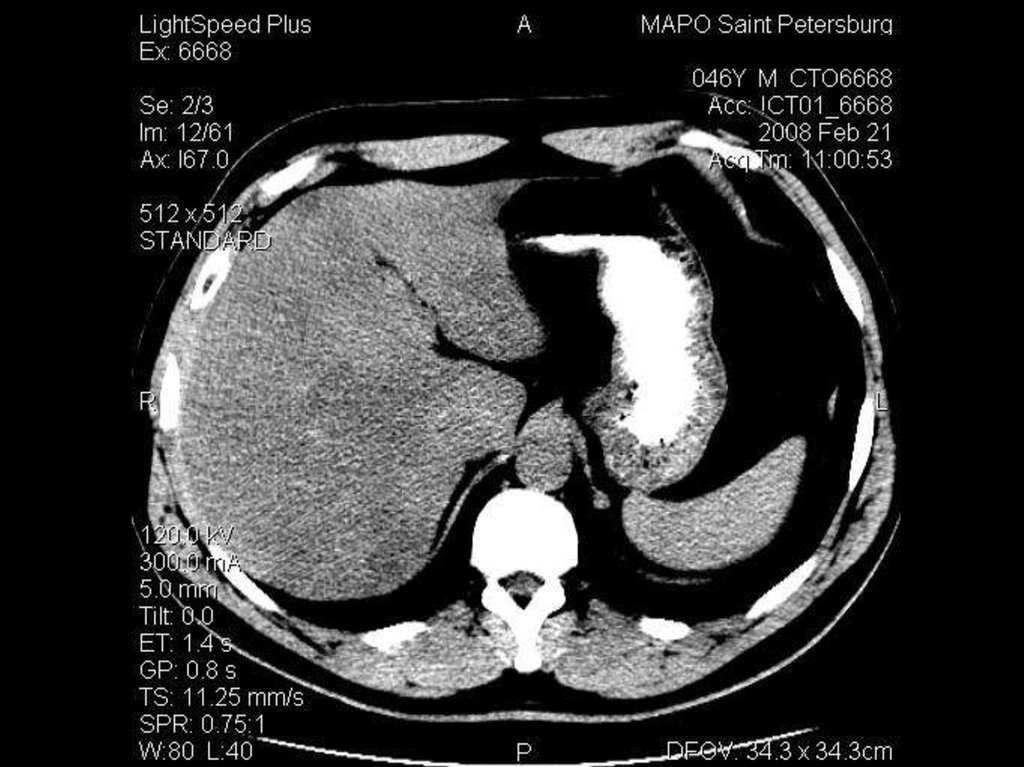

исследование брюшной полости

Ток: 300 мА

Напряжение: 120кВ

Толщина среза: 5.0 мм

Матрица: 512х512

Режим: спиральный, 11.25 мм/с